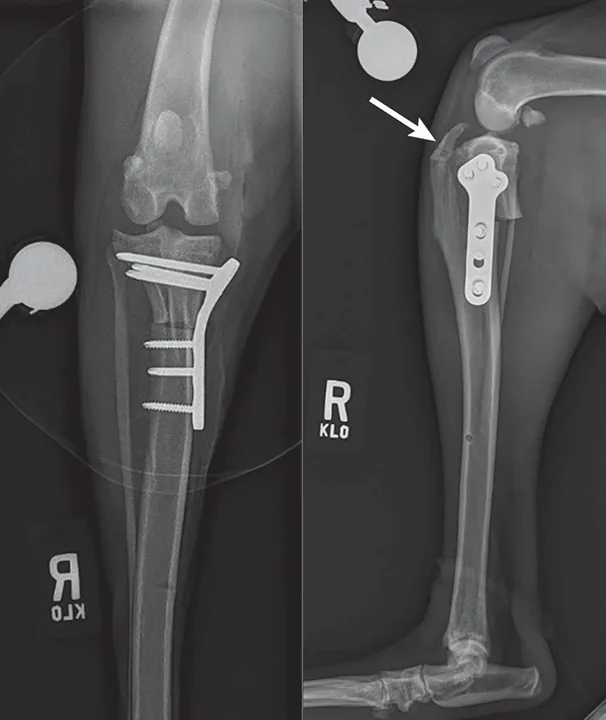

Featured Image

Figure 3

Immediate postoperative radiographs from a 2-year-old spayed medium-size crossbreed dog showing an inappropriately distally positioned TPLO. Distalizing the TPLO reduces the leveling achieved with planned rotation, leaves a narrow tibial crest (arrow), and positions the osteotomy in diaphyseal bone (slower to heal than metaphyseal bone). Also notable is the cranial position of the distal jig pin hole, which may predispose the patient to tibial diaphyseal fracture. This osteotomy position can be compared with that shown in Figure 4, in which the osteotomy position and resultant crest shape are appropriate.